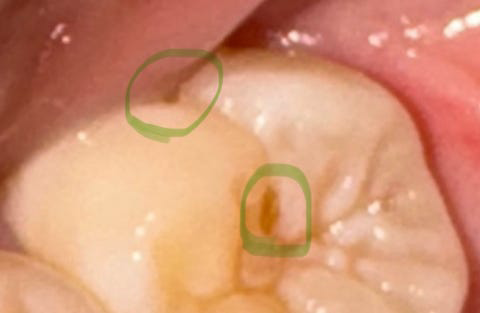

치아에 구멍이 있었는데요 그 근처에 새로운 구멍이 생겼어요

3년 전 저 치아가 자랄때부터 치아의 옆면에 구멍이 있었고요어제 치아의 윗면에 새로운 구멍이 생긴 걸 알게되었어요

다른 치아에는 구멍이 없는데 저 치아에만 구멍이 두 개나 게다가 이어지는 위치에 생기니까 원인이 뭔지 모르겠어요

사진으로 봤을 경우에는 이전에 충전했던 치과재료가 탈락하면서 구멍이 생긴 것으로 보입니다.

치아에 구멍이 존재하게 되면 해당 부위에 이물질이 자주 껴입게 되어 충치가 진행될 수 있기 때문에 해당 부위를 치료해주는 것이 좋습니다.